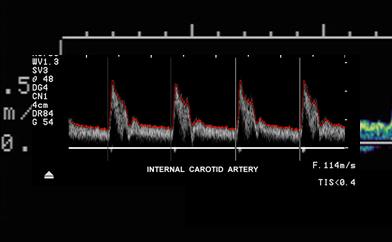

Explain the waveform of the ICA

low resistant - constant forward flow

Forward flow throughout the cardiac cycle

Where is the waveform?

ICA